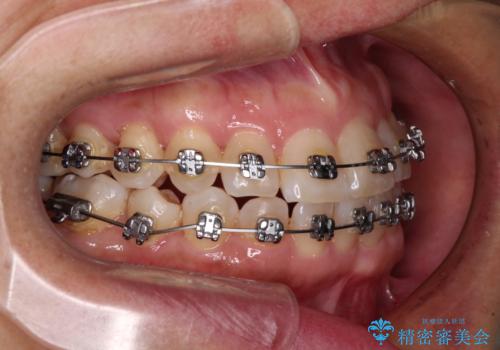

- メタルブラケット

- 1年8ヶ月

- 骨格的な咬み合わせのズレ、前歯のデコボコとクロスバイトを気にして来院された患者様です。

奥歯の噛みにくさが顕著なためマウスピースではなく、ワイヤー装置による矯正治療を行うこととしました。

下顎の正中を歯1本分ずらした位置とすることで、外見上の骨格的なずれをカバーするように計画しました。

クロスバイトを改善したことで、前歯の負担が軽減し、安定して噛めるようになりました。